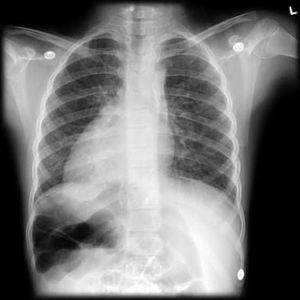

PA view. Whats the diagnosis?

Situs inversus with dextro cardia

Dextrocardia